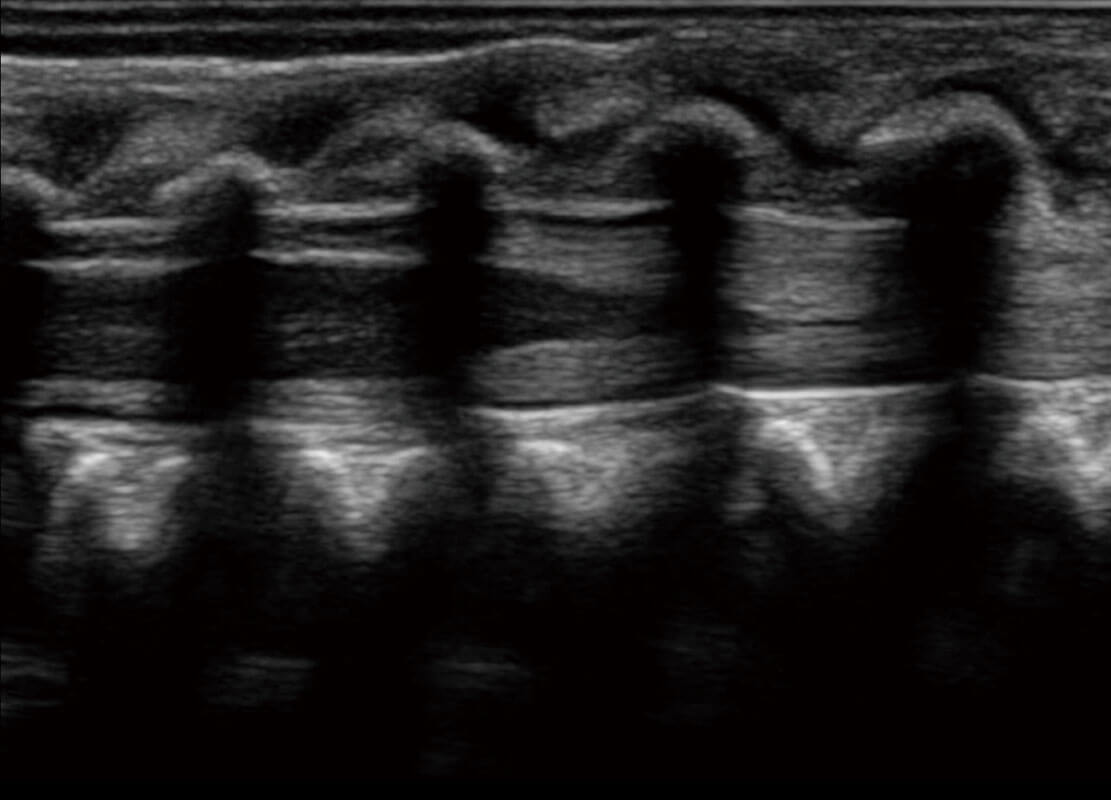

P60搭载宽频带线阵探头、宽景成像、弹性成像技术,为您提供乳腺应用方案。P60支持高频相控阵探头、线阵探头、腹部高频探头、腹部微凸探头等,丰富的探头群搭载敏感的彩色血流成像,适用于新生儿多种脏器检测要求,满足新生儿筛查需求。

新生儿脊髓圆锥